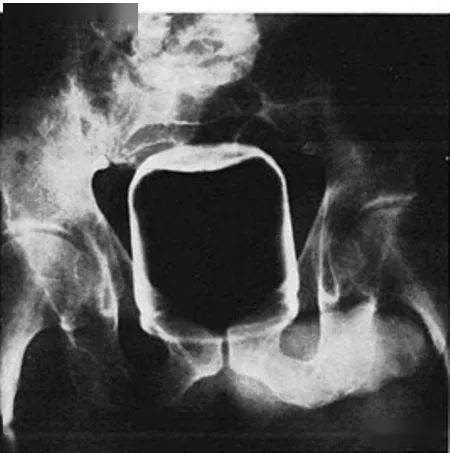

▷圆茄子研究案例的段子手医生表示:圆茄子的形状意味着 , 一旦它的赤道 (也就是最宽的部分)挤进了肛门边缘 ,它就会有往上窜的趋势 。而当这种情况发生的时候 , 嗯…就意味着你要去急诊室了 。